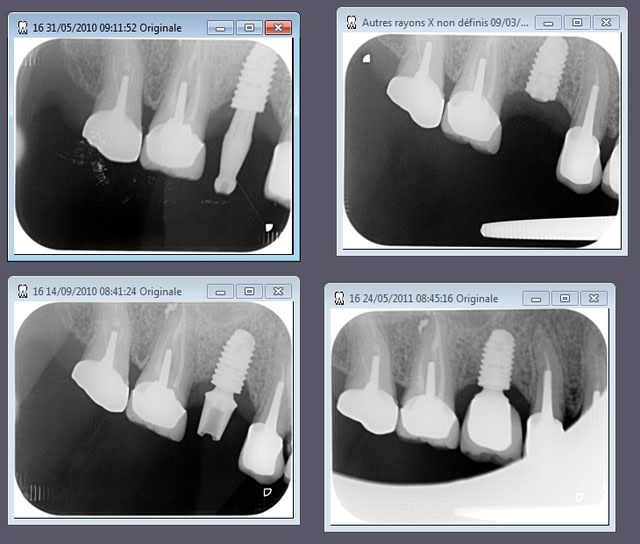

nouvelle radio cette semaine

Tekka n'assume toujours pas.

c'est des krestals? Ça n'a pas l'air dramatique sur la radio. Une petite caractérisation qui me parait logique vu la connexion.

On n'a pas les mêmes critères d'exigences. Perdre 4 mm d'os sur 12 soit 1/3.

Attends, sur ces radios t'as 4 mm de perte osseuse? Les vis de cicatrisation sont en place non? Je devine la jonction implant/vis et y a quasiment pas de perte sur tes dernières radio. Enfin je connais pas bien le krestal et la forme de la vis.

Je veux dire, elle est où la perte osseuse sur cette radio? Mais tu as raison, on ne doit pas avoir les même exigences.

La cratérisation est visible beaucoup plus haute: surtout au sondage. L'os que tu vois est en palatin, en vestibulaire, il n'y a plus rien sur cette même longueur.

Sur la molaire, tu ne vois rien aussi.